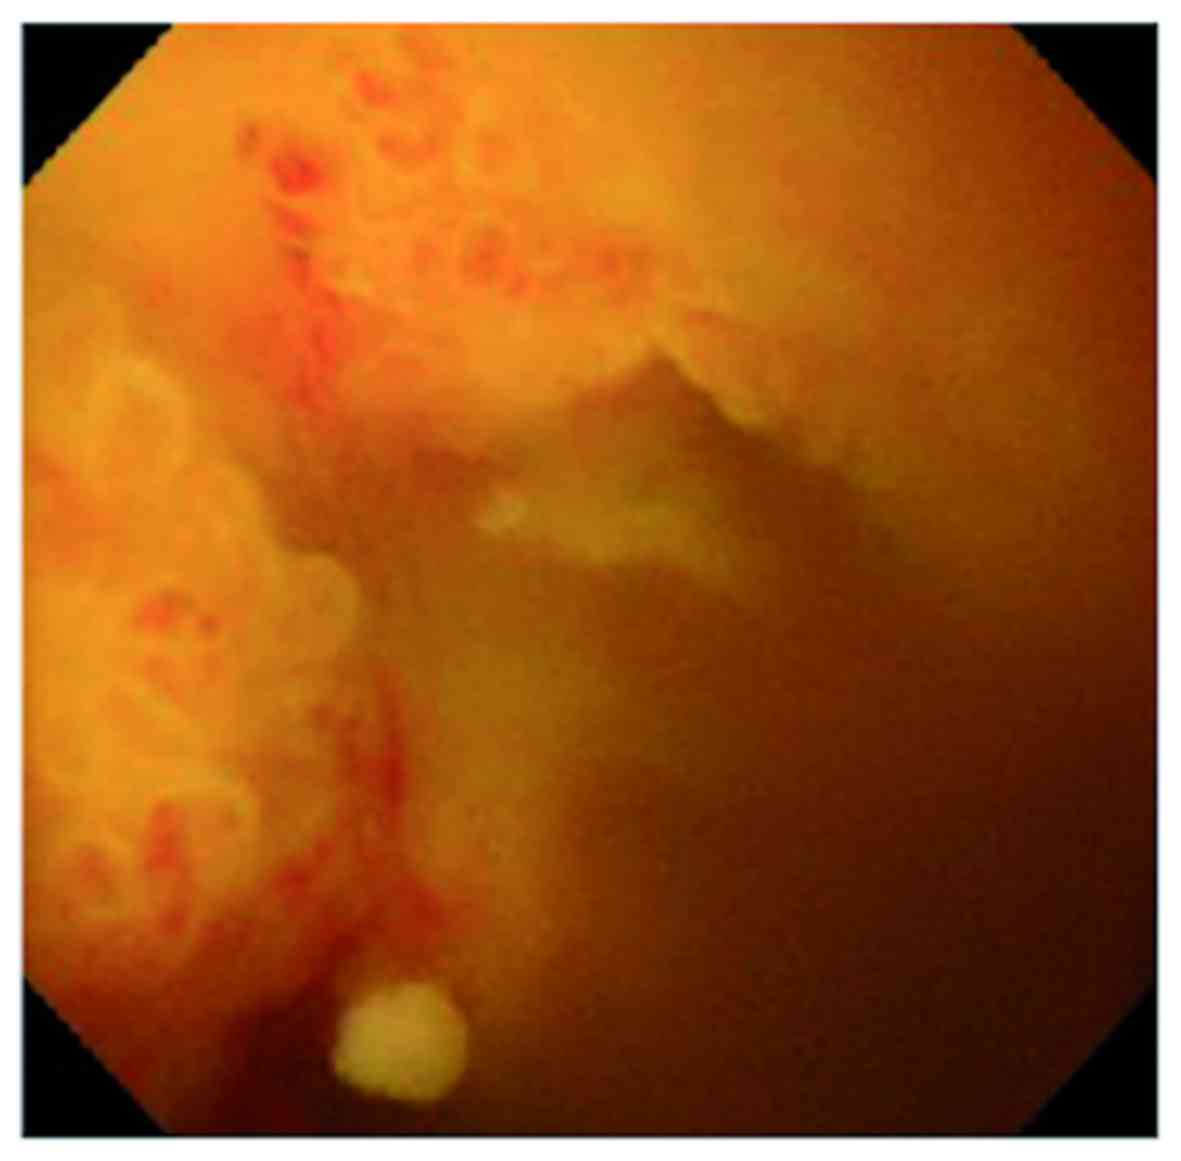

A 64-year-old woman with no particular previous medical history presented with fever lasting for 1 week. No remarkable findings were noted in a physical examination. The serological tests revealed elevated levels of C-reactive protein (13.4 mg/dl; normal range, <0.5 mg/dl), alanine aminotransferase (62 IU/l; normal range, 5–36 IU/l), alkaline phosphatase (816 IU/l; normal range, 110–370 IU/l) and γ-glutamyl transpeptidase (360 IU/l; normal range, 9–50 IU/l). The leukocyte count and serum levels of aspartate aminotransferase, total bilirubin, carcinoembryonic antigen and carbohydrate antigen 19–9 were within the normal range. On computed tomography (CT), a 75-mm cystic mass in the right hepatic lobe and dilatation of the intrahepatic bile duct were detected (Fig. 1A). Following aspiration due to a suspected infectious liver cyst, the patient underwent endoscopic retrograde cholangiography (ERC), which revealed filling defects within the dilated common hepatic duct (Fig. 1B). On peroral cholangioscopy (POCS), a papillary mucin-producing tumor was identified around the orifice of the right hepatic duct, while no obvious tumor was present in the left hepatic and common bile ducts (Fig. 2). Although the small bile duct biopsy from the papillary tumor was not conclusive, extended right hepatectomy was performed for suspected IPNB. On intraoperative frozen section examination, the common hepatic duct margin was tumor-free, while the left hepatic duct appeared to be positive for an intraepithelial tumor with high-grade dysplasia. Despite additional resection of the left hepatic duct, the final resection margin remained focally positive for an intraepithelial neoplasm.

Figure 2.

Findings on peroral cholangioscopy. A papillary tumor with a granular surface is observed in the orifice of the right hepatic duct to the common hepatic duct.